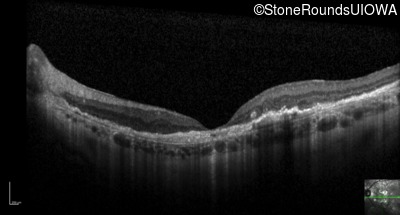

Optical Coherence Tomography - Left - 20/160 -2

Exemplar / OCT Stack

OCT Stack